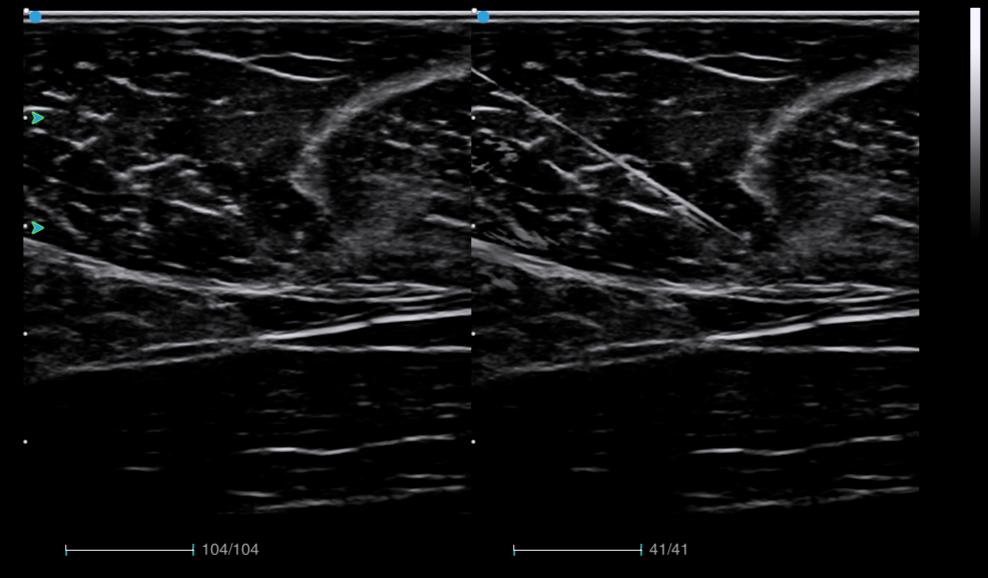

Needle Enhancement improves the visibility of the needle position during biopsy procedure for enhanced operation precision.